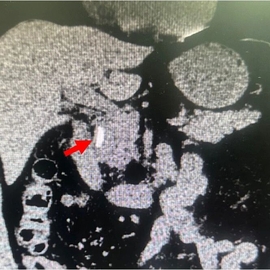

60岁的北湖西路大叔近几天觉得上腹胀痛不适,不想吃东西,大便也未解。